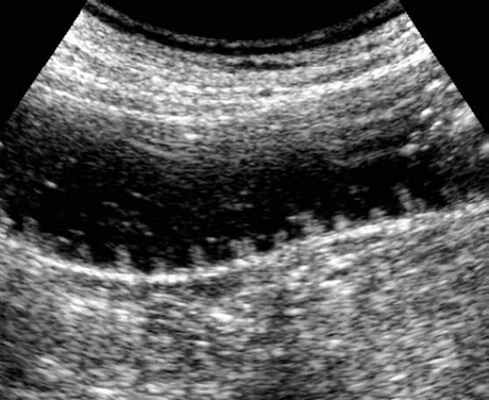

4. Ультразвуковое исследование (УЗИ) широко применяется для оценки разных болезней органов брюшной полости, однако исследований, посвященных диагностике КН, не много. Это может быть связано с тем, что наличие большого количества газа в ЖКТ мешает успешному исследованию кишечника, а также с тем, что спайки в кишке (наиболее распространенная причина кишечной непроходимости) не визуализируются с помощью УЗИ.

Предпосылкой возможного использования ультразвукового (УЗ) метода для диагностики ОКН является избыточное скопление жидкого содержимого в просвете кишки, что позволяет при УЗ-сканировании ее визуализировать.

Избыточное скопление жидкости в кишечнике обусловлено как нарушением эвакуации и всасывания кишечного содержимого, так и пропотеванием жидкости в просвет кишки при развитии ее микроциркуляторных нарушений. В связи с этим жидкое содержимое в просвете кишки, определяемое при УЗИ, называют «симптомом секвестрации жидко

Современные подходы диагностики включают в себя УЗИ брюшной полости или рентгенографию в положении стоя- как первая линия визуализации. В последнее время наблюдается повышенная тенденция использования УЗ-метода, который, как считают некоторые авторы, может заменить классическую рентгенографию. УЗИ позволяет корректно определить наличие тонкокишечной обструкции, при этом зачастую выявляет много рaзличной дополнительной диагностической информации, имеющей определяющее значение для лечебной тактики.

УЗД признаки тонкокишечной непроходимости

Основные УЗ-признаки при непроходмости- это визуализация расширенных петель тонкой кишки, сниженная перистальтика, свободная жидкость между петлями (танга) и в брюшной полости. Также УЗИ иногда позволяет обнаружить причину обструкции, например, опухоль, утолщение стенок терминального сегмента подвздошной кишки при болезни Крона и т.д. УЗИ может решить диагностическую дилемму при неоднозначных рентгенологических признаках на обзорной рентгенограмме брюшной полости. Лимит метода заключается в низкой специфичности при оценки состояния брыжейки, а также зависимость качества диагностики от конституции пациента и опыта оператора.

примеры сонограмм с расширенными петлями тонкой кишки

УЗИ позволяет прекрасно лоцировать свободную жидкость в брюшной полости